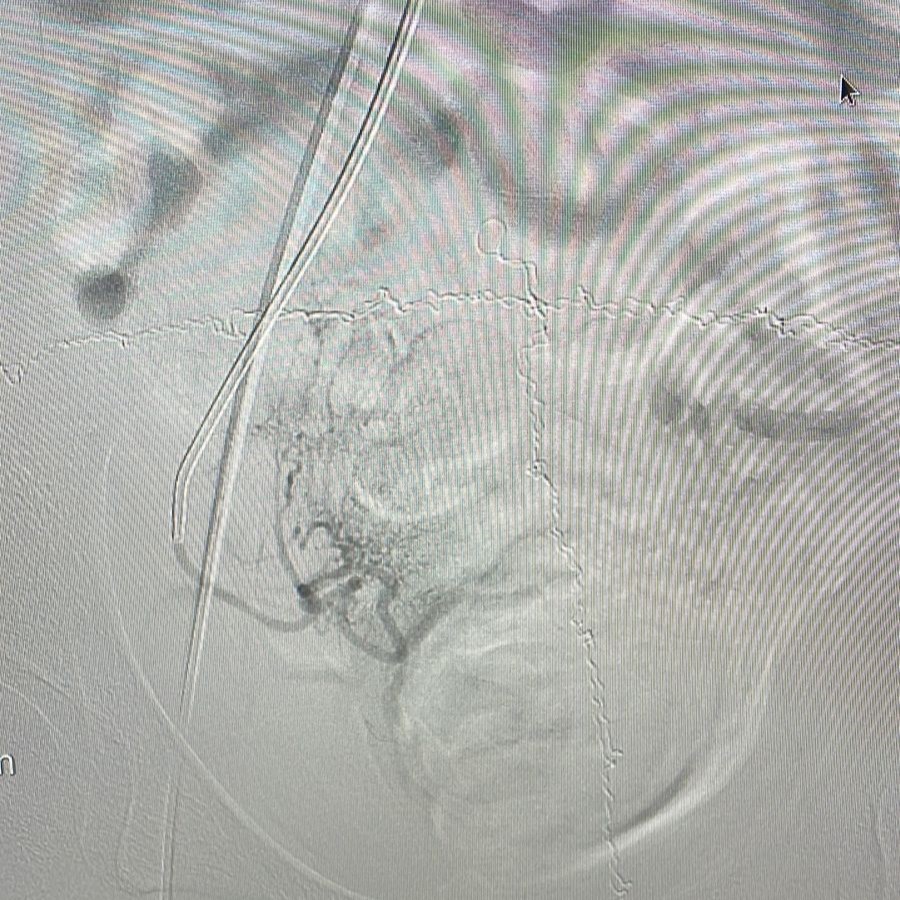

A equipe do Hospital Vaz Monteiro inovou novamente ao realizar, pela primeira vez na região, uma embolização de miomas uterinos, procedimento minimamente invasivo, com punção arterial e cateterização seletiva dos ramos uterinos tanto do lado direito quanto do lado esquerdo, visando administração de embosferas.

De acordo com Dr. Dirceu Dias Barbosa Sobrinho, coordenador da Divisão de Hemodinâmica do hospital, as embosferas são “estruturas desenvolvidas para interromper o fluxo arterial aos miomas, ocasionando sua regressão e desaparecimento, já que os tumores deixam de receber fluxo sanguíneo”.

Havia duas opções no caso: a Histerectomia (retirada total do útero por via abdominal ou pélvica) ou a Embolização. Como não desejava se submeter à histerectomia, a paciente foi encaminhada ao serviço de Hemodinâmica do Vaz Monteiro para avaliação da possibilidade de embolização do mioma. “Felizmente, a ressonância magnética da pelve indicou que se tratava de miomas do tipo subseroso, que respondem muito bem à técnica de embolização”, explica Dr. Dirceu.